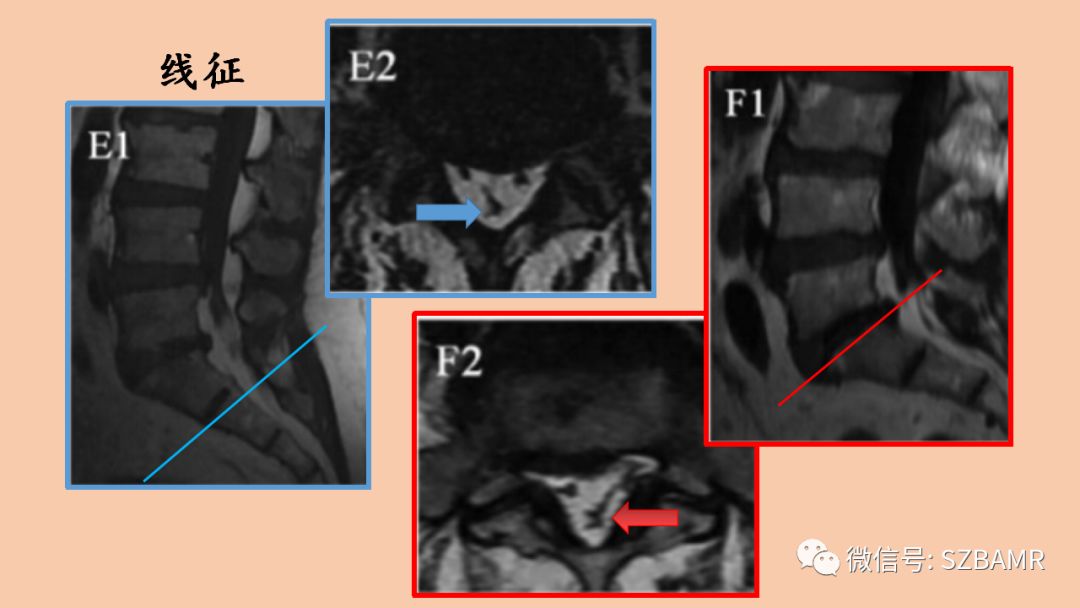

影像表现:胸椎通常堆积于椎管后方,腰椎包绕整个硬膜囊的脂肪信号,压迫硬膜囊,横断面上出现“Y字征”、“星形征”、“线征”或“椭圆征”。